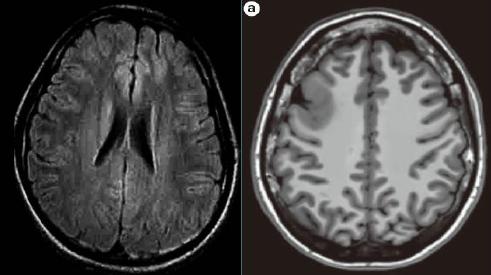

图 癫痫的影像学检查